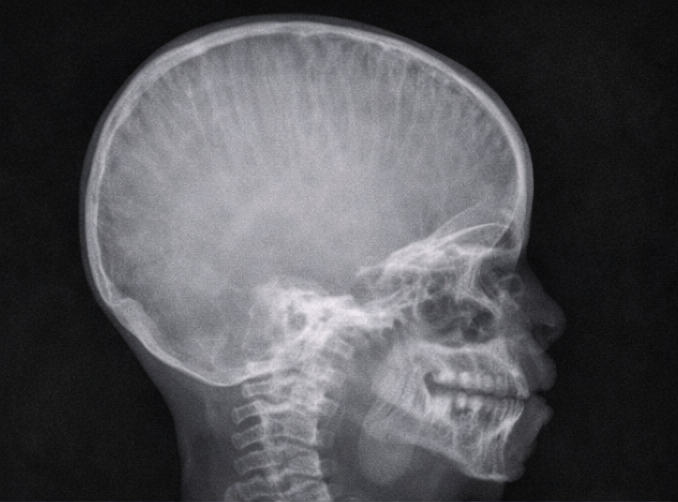

A lateral X-ray of the skull and nasopharynx was obtained to assess adenoid hypertrophy.

The radiograph demonstrated:

Prominent widening of the diploic spaces

Vertical striations giving a characteristic “hair-on-end” appearance

Soft tissue prominence in the nasopharyngeal region

These findings raised suspicion of marrow hyperplasia rather than isolated lymphoid hypertrophy.

Craniofacial involvement is rare and may present with airway obstruction, facial swelling, or radiological abnormalities. The “hair-on-end” appearance on skull radiographs is a classic but uncommon finding in modern clinical practice, reflecting marrow expansion secondary to increased erythropoietic demand [4].